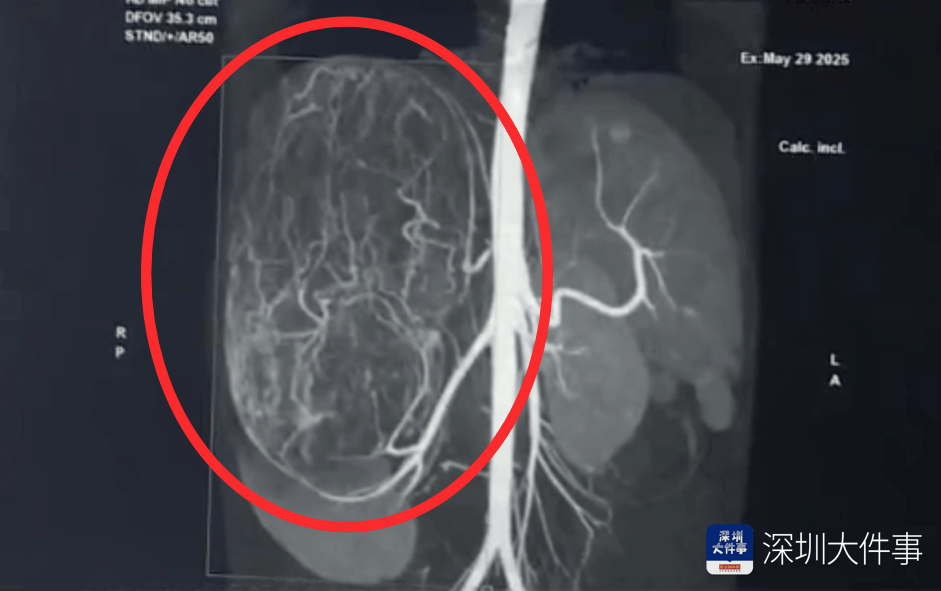

店员试衣间里一句警告,竟救了17岁少女!一家人火速赶到深圳

17岁的汕头女孩婷婷(化名) 平时活蹦乱跳 能吃能睡 身材非常苗条 谁承想 一次平平无奇的逛街买衣服 店员一句善意的提醒 竟让她发现肚子里 有一个大如篮球的肿瘤...